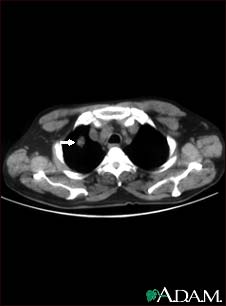

Pulmonary nodule, solitary - CT scan

This CT scan shows a single lesion (pulmonary nodule) in the left lung. This nodule is seen as the light circle in the upper portion of the dark area on the left side of the picture. A normal lung would look completely black in a CT scan.